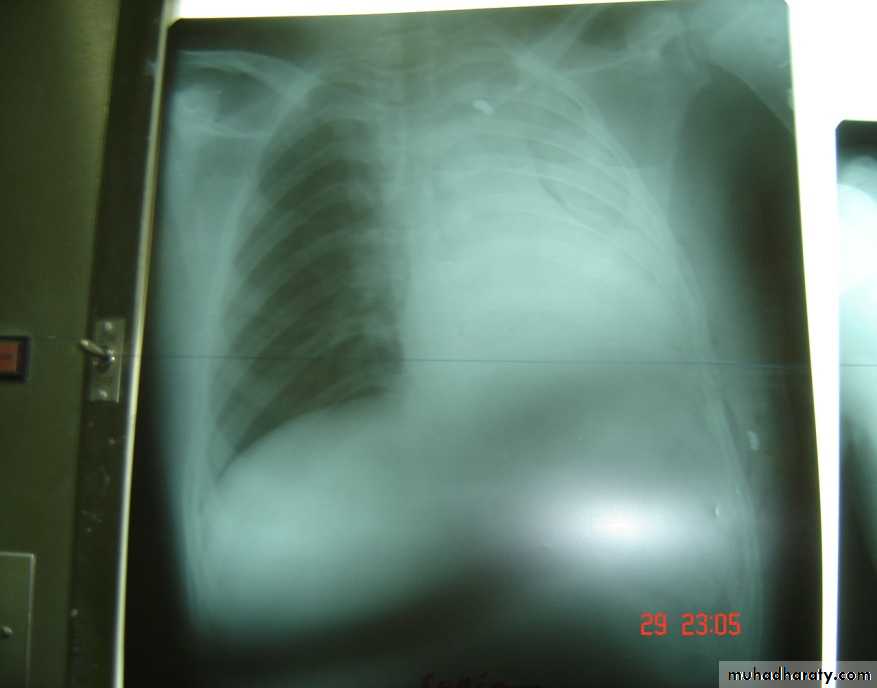

• 3-Pleurl injuries Can lead toA-Pneumothorax which can be partial or complete closed or open sucking or tension pnemothorax . B-Haemothorax may be mild or severe and may be with pneumothorax

Pneumothorax

Collapsed lungTraumatic haemothorax

• 4-Pleural effusion

• Is the accumulation of fluid in the pleural space excessive transudation or exudation of the interstitial fluid from the pleural surface. It is signify pleural or systemic disease .

• Its effect depends on its size (mild , moderate or massive ) & the state of the underlying lung .It is classified as transudate when the protein content is less than 3g% or exudates when protein content is more than 3 gm % .Clinically patients will present with dyspnea & pleuritic chest pain

• Radio logically (concave meniscus sign)